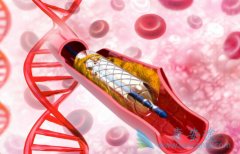

什么是 心脏支架手术 ?可以把心脏支架想象成是个细长的金属笼子,放在血管里就可以把即将堵死的血管撑开,心脏支架非常的细小,直径大约在2~4毫米,长几厘米,有空心、圆柱、网状金属管,一般都是用钛合金制成,是世界上最昂贵的一种金属。 心脏支 ...

不少人都听过心脏支架手术,这种手术堪称是当代心脏病学最伟大的一项发明。你知道这个小小的支架是怎么放到心脏里去的吗? 心脏支架 是通过介入手术的方式植入到人体的,我们可以从心脏介入手术可是说起,这样更好理解。心脏介入原理其实并不复杂。 ...

为了改善冠心病介入治疗短期和长期的疗效与安全性,所以研发了支架。第一代支架是金属裸支架,使冠心病介入治疗前进了一大步,使介入治疗变得非常安全,当血管发生严重狭窄时单纯球囊扩张预处理后,再用支架把血管完全撑开,就能解除心肌缺血危险,而且 ...